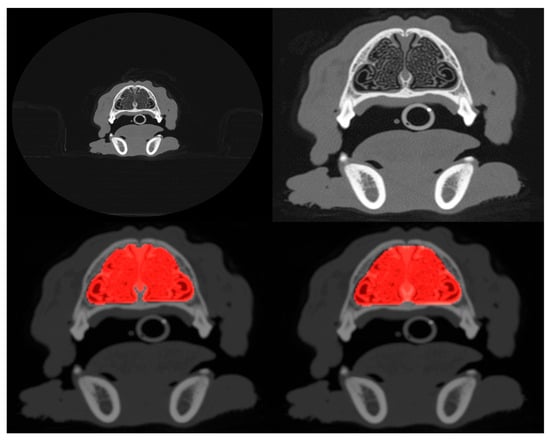

The results of segmentation using the ResUNet++ model are shown in Table 2, and an example segmentation is shown in the bottom-right panel of Figure 1. Considering that a Dice coefficient of 1 indicates complete agreement between the predicted and ground truth segmentation masks, the findings reveal the highly accurate identification of nasal cavities by the model. Reliable segmentation is key for the success of the final phase where classification is carried out on these identified areas. Once again, the metrics show that performance degrades slightly when the model is trained and tested on the cropped scans. Figure 2 (middle panel) shows the validation loss and Dice coefficient curves for the segmentation model.

Figure 1. Example of uncropped (top-left) and cropped (top-right) scans projected onto the axial plane. Both cropped and uncropped images were tested in slice selection and segmentation, but only cropped images were used for pathology classification. The bottom-left panel shows the manually defined ground truth mask (highlighted in red) that segments the nasal cavity of the slice shown in the top-right, and the bottom-right panel shows the mask predicted by the segmentation model.